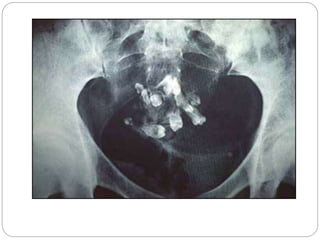

Cystic neuroblastoma/

Ganglioneuroma(rare)

 Over half of them arise in the adrenals, but 30%

can arise

 from sympathetic tissue elsewhere in the

abdomen

 Calcification has been noted to occur in over 50%

of Cases

 Ganglioneuroma is a mature form of neurogenic

tumour.

 Calcification helps in suggesting a diagnosis of

neurogenic tumour

Cystic neuroblastoma/ Ganglioneuroma(rare)  Overhalf of them arise in the adrenals, but 30% can arise  from sympathetic tissue elsewhere in the abdomen  Calcification has been noted to occur in over 50% of Cases  Ganglioneuroma is a mature form of neurogenic tumour.  Calcification helps in suggesting a diagnosis of neurogenic tumour